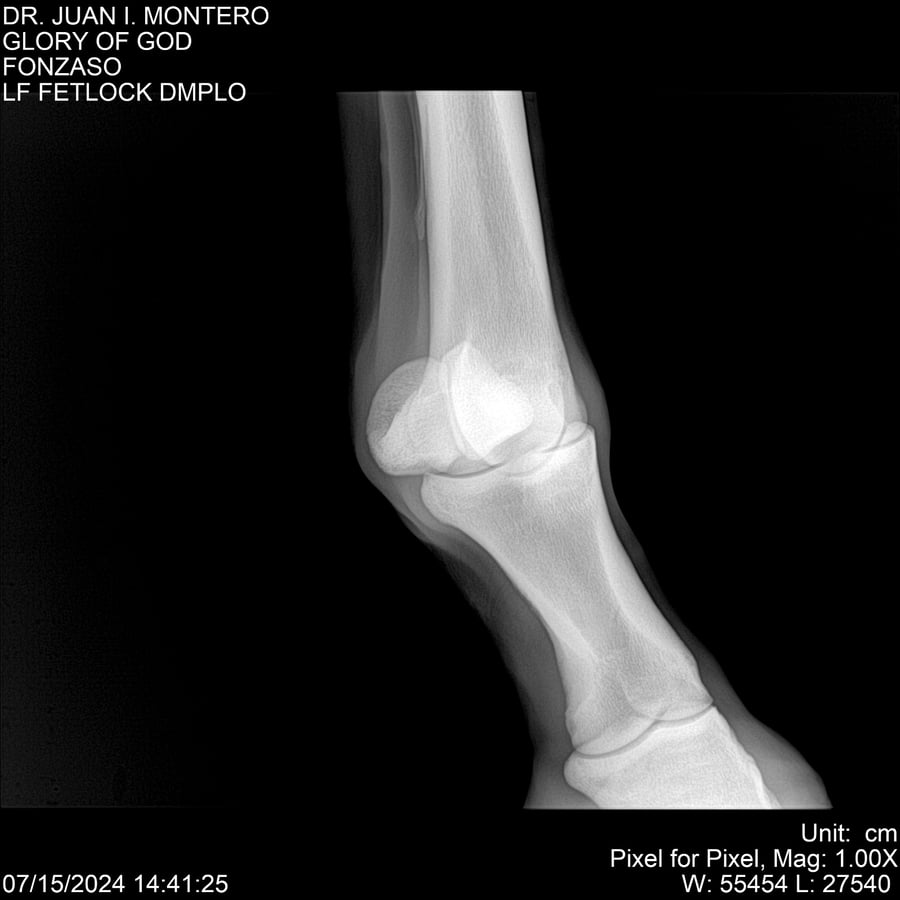

LOTE 10, GLORY OF GOD 🔥 🔥 🔥 Lote Anterior Volver al remate Lote Siguiente Ficha Contacto Montevideo - Ficha del Lote Identificador: #281389 Categoría: Yeguarizos Montevideo - 115 Visualizaciones ClicData Contacto Empresa: Abelenda N. R., Walter Hugo Nombre*: Teléfono* : E-mail* : Mensaje Enviar Registrese gratis Este contenido Exclusivo está disponible sólo para usuarios registrados Ingresar